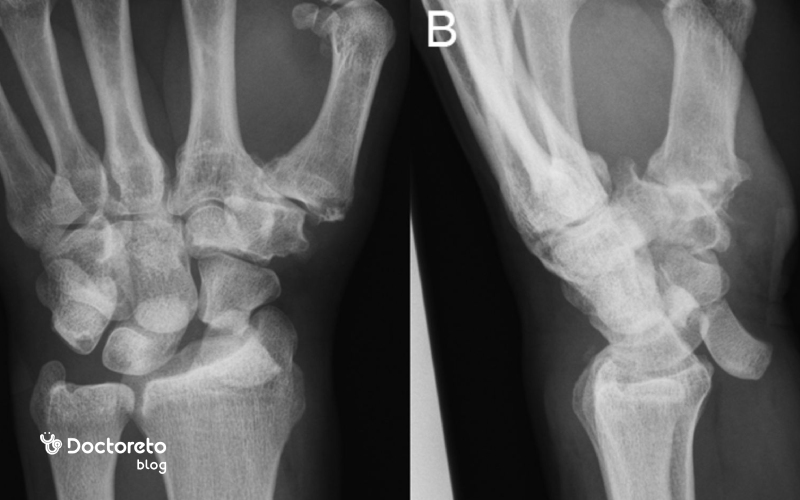

عکس در رفتگی مچ دست

این تصویر رادیوگرافی از مچ دست در دو نما، نمای قدامیـخلفی و نمای جانبی، برای بررسی ساختار استخوانها و مفاصل مچ استفاده میشود و میتواند تغییراتی مانند ناهماهنگی استخوانهای کارپ، کاهش فاصله مفصلی، زوائد استخوانی یا علائم آرتروز و آسیبهای لیگامانی را نشان دهد. چنین تصاویری معمولاً در ارزیابی درد مزمن مچ دست، محدودیت حرکتی، سابقه ضربه یا شک به ناپایداری مفصل به کار میروند و به پزشک کمک میکنند تا وضعیت استخوان رادیوس، اولنا و استخوانهای کوچک مچ را از نظر شکستگی، دررفتگی یا تغییرات دژنراتیو بررسی کند. تفسیر دقیق این رادیوگرافی باید توسط پزشک و با در نظر گرفتن علائم بالینی و در صورت لزوم تصویربرداری تکمیلی انجام شود.